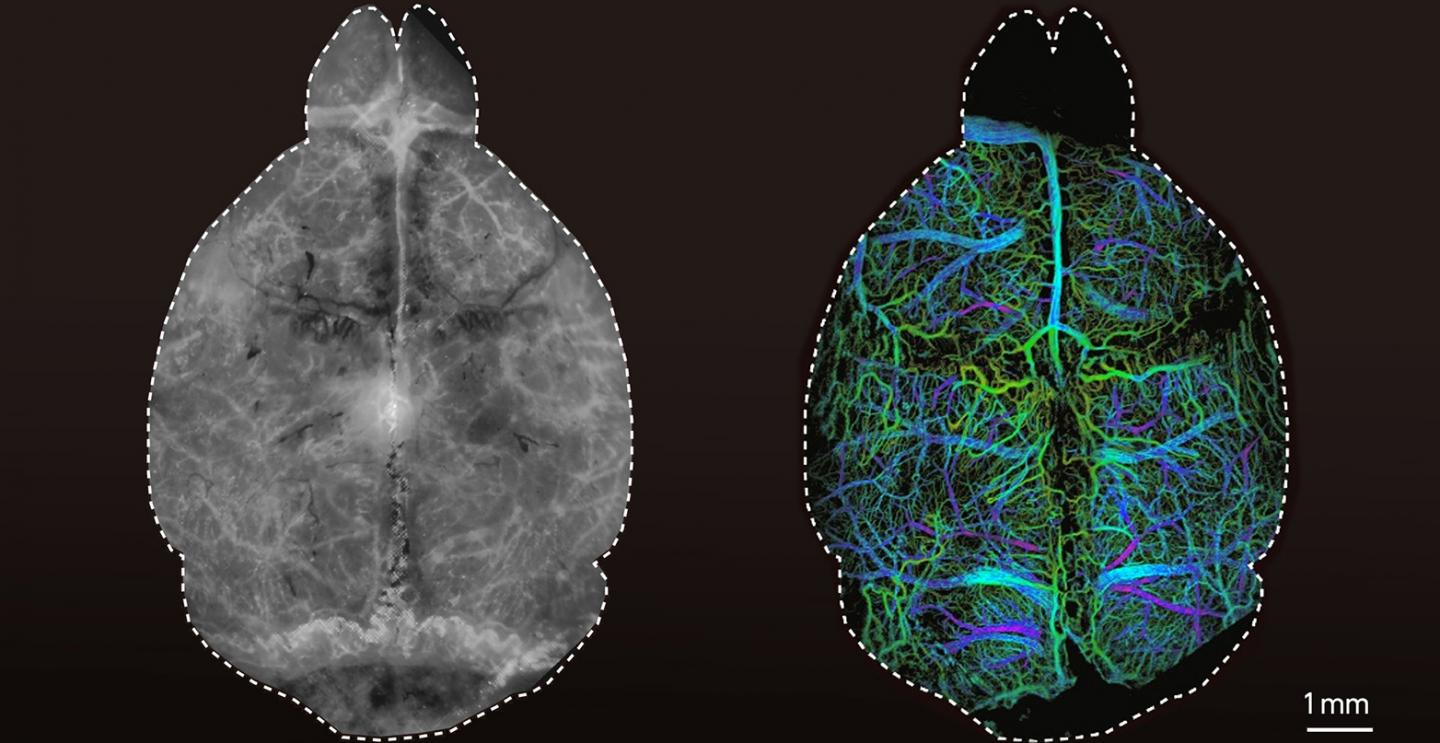

image: Left: Conventional fluorescence images of a mouse brain. Right: An image taken with the new diffuse optical localization imaging (DOLI) method.

ETH Zurich, University of Zurich / Daniel Razansky

The researchers first tested the new technique using synthetic tissue models that simulate the properties of brain tissue, demonstrating that it is possible to acquire microscopic images at four times the penetration depth of conventional fluorescence microscopy approaches. Razansky and his team then injected living mice with microdroplets encapsulating fluorescent quantum dots as a contrast agent. They were then able to localize these droplets individually in the living brain using the new technique.

"For the first time, we were able to clearly visualise the microvasculature and blood circulation deep in the mouse brain entirely noninvasively," says Razansky. In addition, the researchers from ETH Zurich and the University of Zurich observed that the size of the imaged microdroplets depends on how deep they are located in the brain. This makes the DOLI technique capable of three-dimensional imaging.